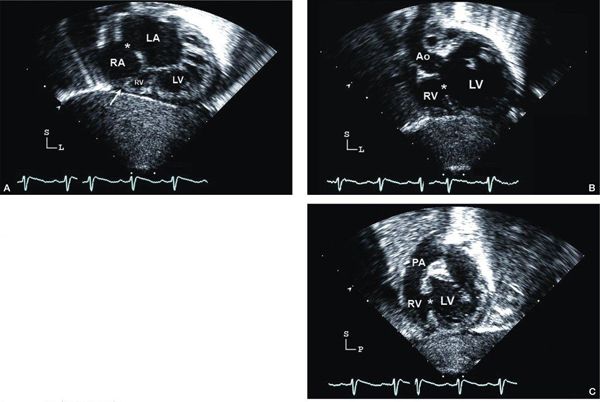

Subcostal four-chamber (coronal) view Subcostal examination begins with a determination of abdominal viscera and atrial situs in all patients. Subcostal four-chamber (coronal) views will show dilation of the RA with absence of the connection to the RV (Fig. 12.2A [Video 12.1A]). As foreshortening of the RV may occur in this plane, short-axis (sagittal) plane imaging is useful for “three-dimensional” assessment of right ventricular size. The atrial septum is best visualized from subcostal imaging planes, and characterization of the ASD should be performed. Prominent Eustachian valve tissue may be present but typically does not contribute to obstruction. Color Doppler will show a right-to-left shunt from the RA to the left atrium (LA) and no flow from the RA to the RV. It is unusual for the ASD to be restrictive, but pulsed-wave Doppler interrogation should be used to evaluate the RA-to-LA gradient, tracing the signal over three cardiac cycles to determine a mean gradient. An atrial shunt is obligatory for survival; therefore, a restrictive ASD may result in severe hemodynamic compromise requiring urgent septostomy. Evaluation of the great arteries from multiple imaging planes to determine ventriculoarterial connections is important (Fig. 12.2B–C [Video 12.1B, C]). An enlarged, posterior great artery (PA) that bifurcates early is consistent with transposed great arteries (ventriculoarterial discordance) (Fig. 12.3A–B [Video 12.2A]). Examination of the ventricular septum may provide information on the size and location of the VSD, but orthogonal views will be needed. In tricuspid atresia, the VSD is usually muscular; rarely, the VSD can be doubly committed and subarterial or outlet in nature. The mitral valve and left ventricular function can be assessed initially from the four-chamber subcostal plane.

Figure 12.2. Tricuspid atresia with normally related great arteries; subcostal views. A: “Four-chamber” (coronal) view showing moderate-sized secundum atrial septal defect (asterisk), atretic tricuspid valve (arrow), hypoplastic right ventricle (RV), and dilated left ventricle (LV). B: Four-chamber view, angled anteriorly, illustrating the large ventricular septal defect (asterisk). Aortic (Ao) origin from LV in normally related great arteries. C: Short-axis (sagittal) view showing anterior RV, posterior LV, and muscular ventricular septal defect (asterisk). In normally related great arteries, the pulmonary artery (PA) arises anteriorly from the RV and bifurcates early. LA, left atrium; RA, right atrium (Video 12.1).

Subcostal short-axis (sagittal) view Subcostal short-axis views demonstrate the absent connection between the floor of the RA and the hypoplastic RV. Orthogonal views are very useful for evaluation of the atrial septal anatomy. Again, the right-to-left shunt should be unrestricted in the setting of an adequate interatrial communication. Rightward angulation of the transducer facilitates evaluation of the absent communication between the RA and the hypoplastic RV, and the size of the RV is more easily assessed in the subcostal short-axis view than in the four-chamber imaging plane (Figs. 12.2C and 3C–D). Evaluation of the size of the VSD between the LV and hypoplastic anterior RV is important for documenting sites of obstruction to arterial outflow. Careful sweeps from right to left are important to obtain complete information about the location and degree of right ventricular outflow obstruction. Assessment of the ventriculoarterial connection is performed from the short-axis view; again, the proximal bifurcation of the PA should be assessed. The presence of parallel great arteries suggests transposition (ventriculoarterial discordance). A small anterior aorta should prompt a careful evaluation for coarctation of the aorta from additional views.